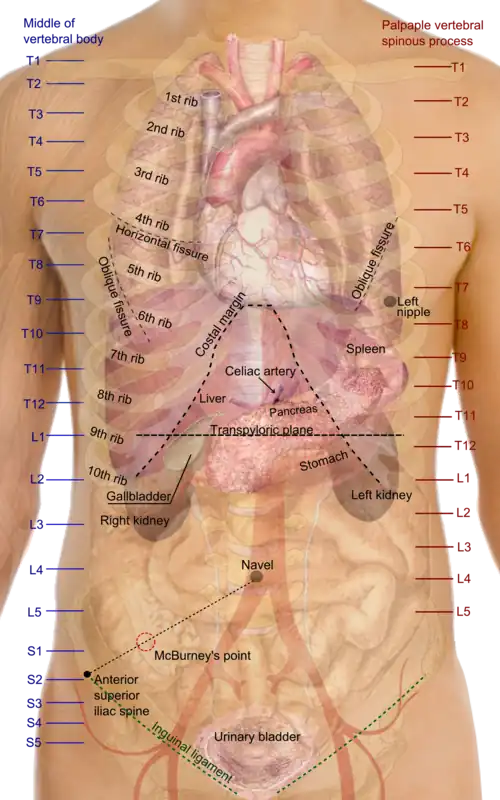

Die Aorta ist die größte Schlagader (Arterie) des Körpers. Beim erwachsenen Menschen hat sie in der Regel einen Durchmesser von etwa 2,5–3,5 cm und eine Länge von 30–40 cm. Sie hat die Form eines aufrechten Spazierstocks mit einem bogenförmigen Anfang und einem geraden Verlauf nach unten bis in den Beckenbereich.

In der Anatomie, Chirurgie und bei bildgebenden Verfahren unterscheidet man zur besseren Orientierung folgende Aortenabschnitte:

- Aufsteigende Aorta (Aorta ascendens), die von der linken Herzkammer aus nahezu senkrecht nach oben verläuft und von dieser durch die Aortenklappe getrennt ist. Sie liegt vollständig in der Herzbeutelhöhle und ist nur wenige Zentimeter lang. Der leicht bauchig erweiterte Anfangsteil der Aorta (Aortenbulbus oder Bulbus aortae) besteht aus den drei Sinus aortae (auch Sinus Valsalvae), die vom Schließungsrand des jeweiligen Aortenklappensegels und der Aortenwand begrenzt sind. Aus dem vorderen und linken Sinus entspringen unmittelbar am Herzen die Herzkranzgefäße (Arteriae coronariae) zur Versorgung des Herzmuskels. An der aufsteigenden Aorta befindet sich eine Umschlagstelle des Herzbeutels, die als Crista aortae ascendentis (Rindfleischfalte) bezeichnet wird.

- Aortenbogen (Arcus aortae) als Fortsetzung der senkrecht aufsteigenden Aorta. Aus dem Aortenbogen gehen unter anderem die Schlagadern zur Versorgung von Kopf und Armen ab. Die drei wichtigsten Abgänge des Aortenbogens sind der Truncus brachiocephalicus, die Arteria carotis communis sinistra und die Arteria subclavia sinistra.

- Absteigende Aorta (Aorta descendens), die bis in den Beckenraum zieht und sich dort in die beiden großen Beckenarterien aufteilt. Sie ist ca. 30 cm lang und wird noch einmal in Unterabschnitte aufgeteilt:

- Brustaorta (Aorta thoracica), die vollständig im Brustraum liegt. Sie gibt Gefäße zum Herzbeutel, zu den Zwischenrippenräumen, zur Speiseröhre und zur Eigenversorgung des Lungengewebes ab (nicht zu verwechseln mit den Gefäßen, die zur Sauerstoffaufnahme durch die Lungen führen, diese stammen aus dem kleinen Blutkreislauf). Nach dem Durchtritt durch den Hiatus aorticus des Zwerchfells wird aus der Brustaorta auf der Höhe des zwölften Brustwirbels die

- Bauchaorta (Aorta abdominalis), die sich anhand des Abgangs der beiden Nierenarterien (Arteriae renales) wiederum in zwei Segmente unterteilen lässt:

- Bauchaorta oberhalb der Nierenarterien (Aorta abdominalis suprarenalis), die sofort nach Zwerchfelldurchtritt den Truncus coeliacus zur Versorgung von Magen, Milz, Zwölffingerdarm, Bauchspeicheldrüse und Leber abgibt. Ein weiterer Abgang (Arteria mesenterica superior) versorgt den Hauptteil des Darms und der übrigen Verdauungsorgane.

- Bauchaorta unterhalb der Nierenarterien (Aorta abdominalis infrarenalis), aus der Gefäße für die unteren Darmabschnitte (Arteria mesenterica inferior), den Enddarm und einige Beckenorgane abgehen. Dieser Aortenabschnitt teilt sich schließlich auf Höhe des vierten Lendenwirbels im Becken in die beiden großen Beckenschlagadern (Arteriae iliacae communes) auf.